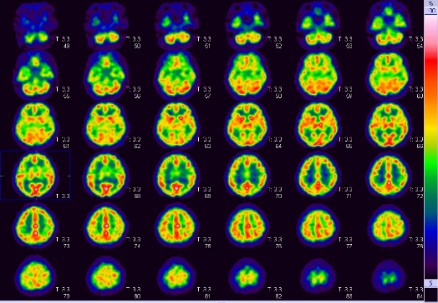

FDG-PET検査

この検査は、てんかんの病巣診断、心サルコイドーシスの診断、早期胃がんを除く全ての悪性腫瘍・悪性リンパ腫の診断等に有用とされています。当院では主にてんかんの方の検査を多く行っていますが、その他の上記疾患の検査も行っています。

使用する放射性医薬品は18F-FDGです。当院では投与直前から調光下で安静にベッドに横になっていただき、投与後は頭部検査では45分後から15分程度、全身では60分後から30分程度、心臓では全身の撮像後に15分程度の撮像を行います。